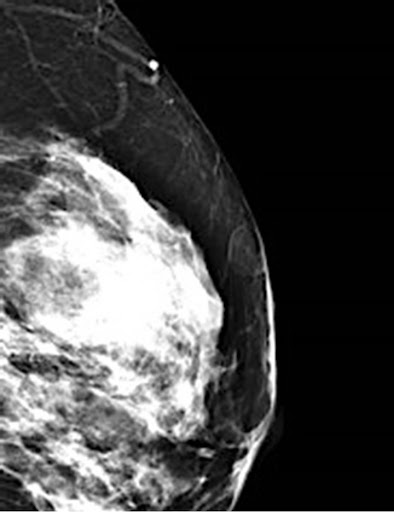

Up to 10% cash back wide local excision is the gold standard treatment for severe hidradenitis suppurativa but remains challenging due to high rates of complications. Wide local excision with skin grafting, skin flap transfer, and primary closure has been common. Abstract wide local excision is the gold standard and only potential curative therapy for recalcitrant hidradenitis suppurativa.

In excision, the goals are the complete removal of diseased tissue and the prevention of new hs lesions in future. Wide local excision is the gold standard and only potential curative therapy for recalcitrant hidradenitis suppurativa. The choice of the surgical borders for radical excision is important.

Wide local excision is the gold standard and only potential curative therapy for recalcitrant hidradenitis suppurativa. Hidradenitis suppurativa (hs) is a chronic inflammatory skin disease that affects patients' quality of life (qol). Objectives we sought to measure the impact of wide local excision.